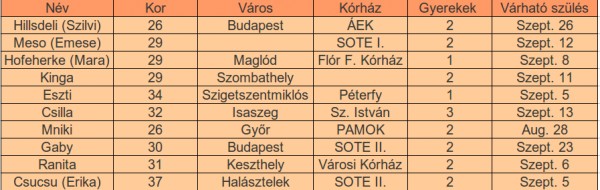

jelentem, az én időpontomat i s lhet módosítani ma vagyunk 8+5 naposak szeptember 10-re vagyok most kiirva!!most 2,09 cm..pöttömke. éshallottam dobogni végre a szivét!!!